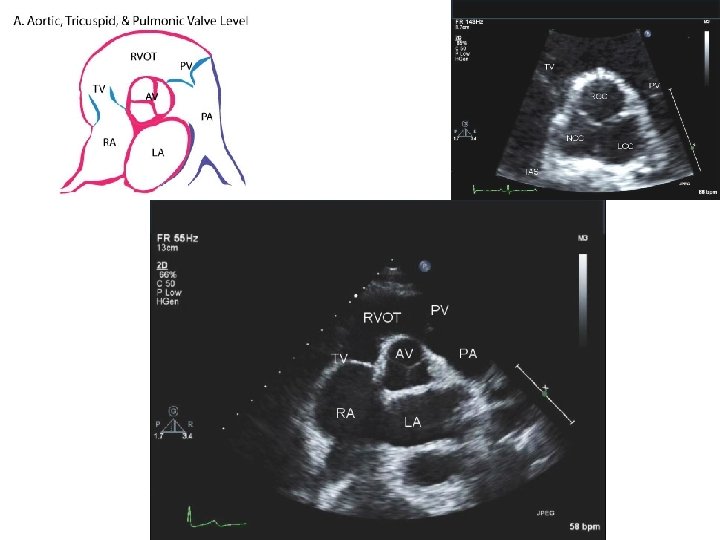

PARASTERNAL SHORT AXIS

PARASTERNAL SHORT AXIS - AT PULMONARY ARTERY BIFURCATION LEVEL